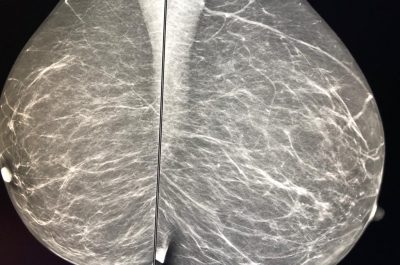

Mammografia 3 D, scoprire i tumori “invisibili”: ecco come funziona e quando è necessaria la tomosintesi